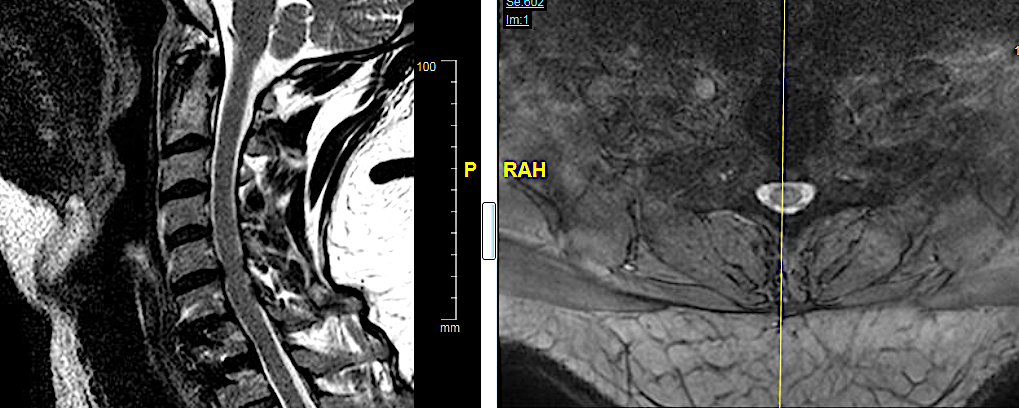

CASO CLÍNICO 1: HERNIA DISCAL TH1-TH2 MIGRADA CAUDALMENTE (con engrosamiento calcificado de LVCP hasta Th2-Th3).

Paciente de 58 años con dolor radicular refractario de >6 meses en MSD, acompañada de pérdida de fuerza en la musculatura intrínseca y atrofia muscular. EMG presenta afectación severa crónica en raíces C7-C8-Th1 derechas.

Obsérvese HDTh1-Th2 con migración caudal retrosomática (Th2)

Obsérvese el engrosamiento de LVCP de aspecto calcificado

El compromiso anterior del canal (a pesar de la radiculopatía severa en MSD) me obliga a plantearme un abordaje anterior con posibilidad de ampliar el campo a través de una esternotomía.